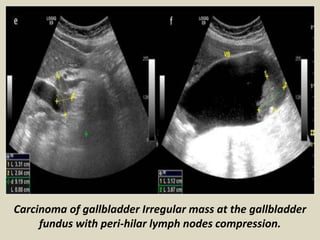

Carcinoma of gallbladder Irregular mass at the gallbladder

fundus with peri-hilar lymph nodes compression.

Carcinoma of gallbladderIrregular mass at the gallbladder fundus with peri-hilar lymph nodes compression.